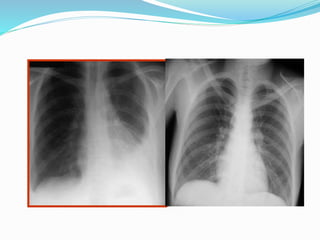

 x ray

The fluid itself can be seen at the bottom of the lung

or lungs, hiding the normal lung structure.

If heart failure is present,

 the x-ray shadow of the heart will be enlarged

 Chest Radiography :The posteroanterior and lateral

chest radiographs are still the most important initial

tools in diagnosing a pleural effusion.